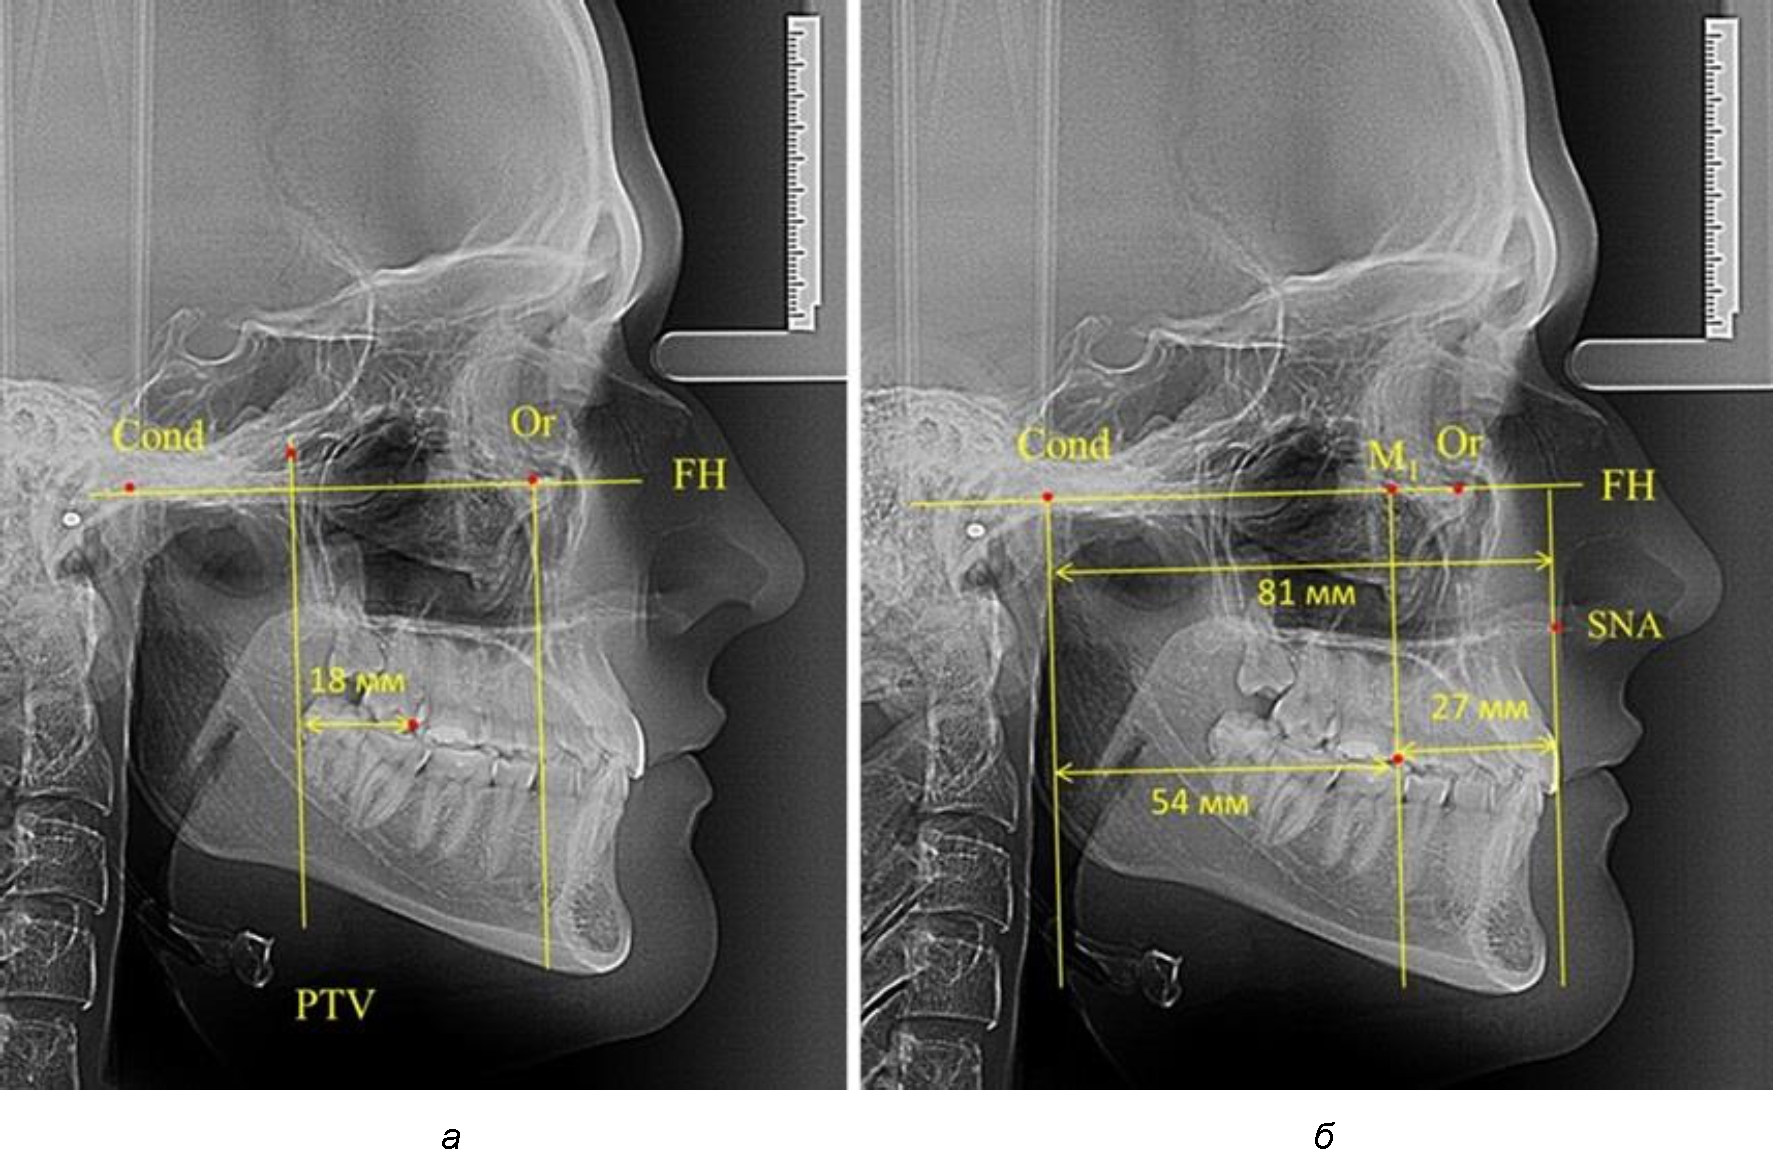

Так, при расстоянии от крыловидной вертикальной плоскости PTV до дистальной поверхности верхнего первого постоянного моляра в 13 мм сагиттальный размер гнатического отдела был 82 мм. При этом отношение кондилярно-спинального расстояния к кондилярно-молярному размеру (54,5) было близким к коэффициенту 1,5, что представлено на рис. 2.

Рис. 2. Особенности положения первых моляров по R. E. McDonald (а) и по предложенному методу (б) при уменьшенном молярно-крыловидном расстоянии